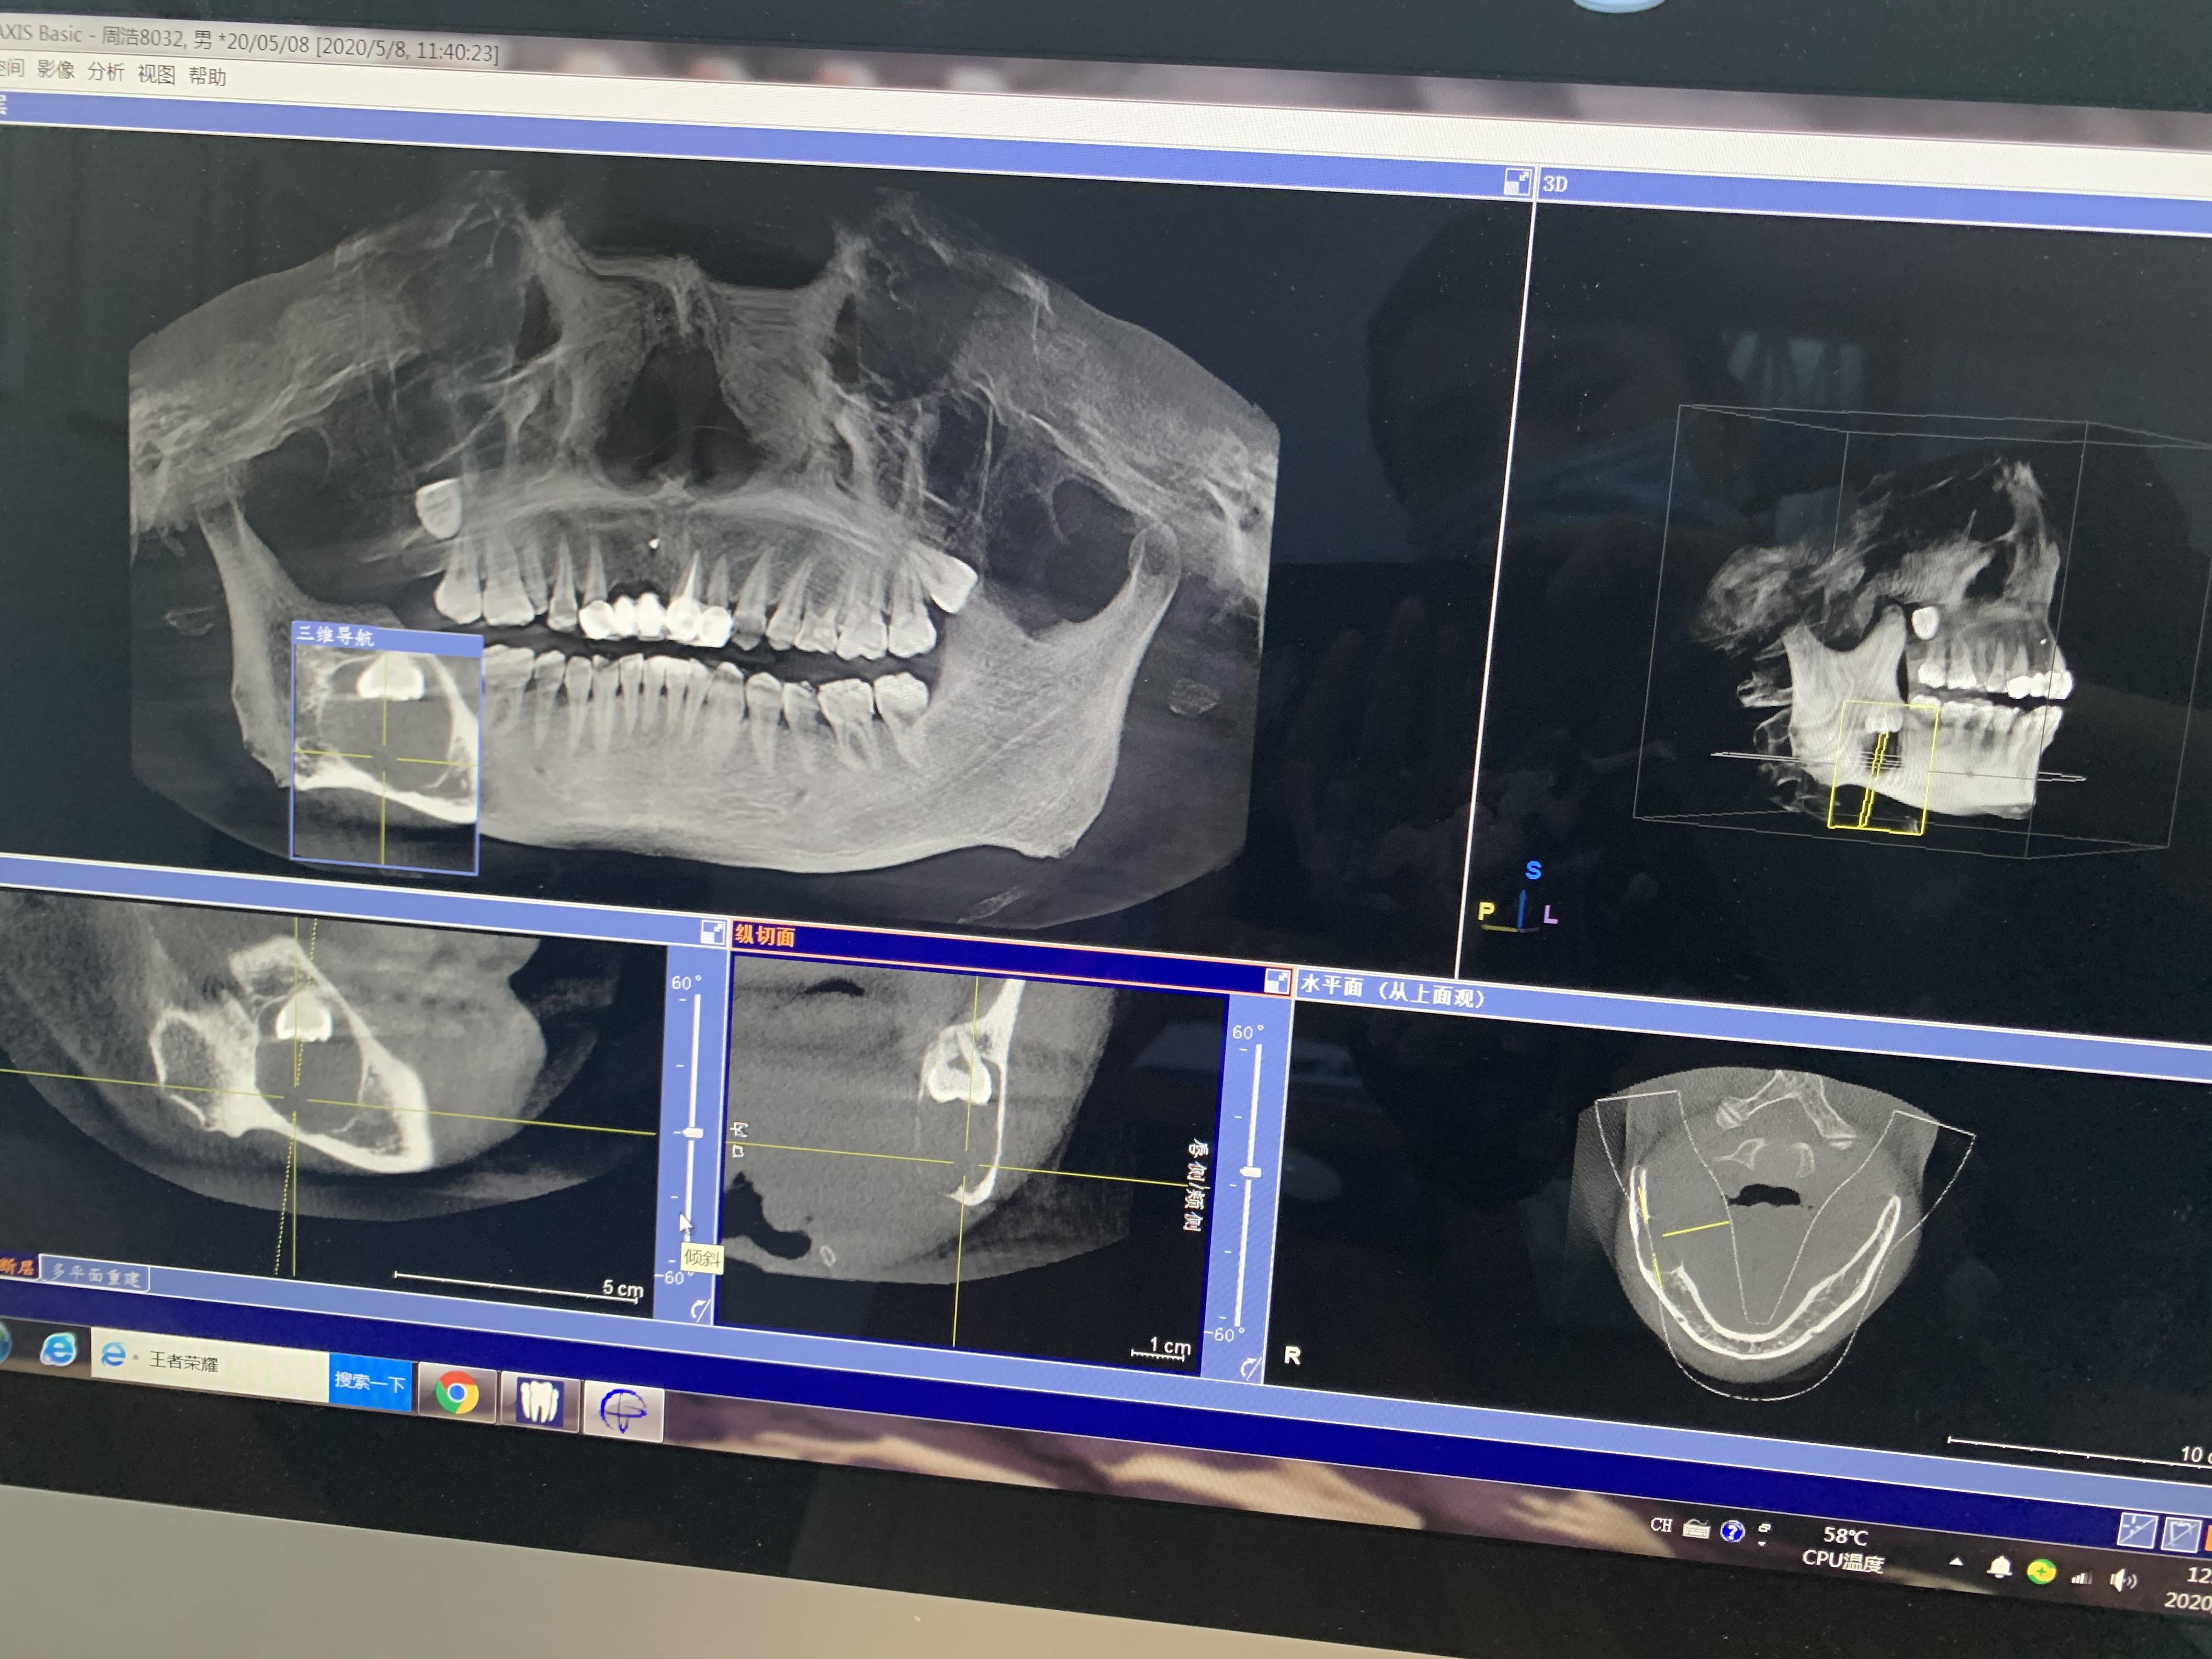

方框內(nèi)圓形的就是囊腫,從邊緣看,骨頭已經(jīng)很薄了

右下頜囊腫,倒阻生牙

下午1點(diǎn)半,片子拍好拿到了,王醫(yī)生看過后告訴我:

1.根據(jù)片子來看,囊腫確實(shí)挺大,神經(jīng)已經(jīng)被壓迫到一邊了,做完手術(shù)后右下巴和嘴唇會出現(xiàn)麻木的情況,當(dāng)然,這種情況后面也會慢慢恢復(fù),但每個(gè)人的恢復(fù)情況不一樣,所以不敢說多久可以恢復(fù);

2.根據(jù)片子來看,可以不做開窗,開窗很多時(shí)候也是為了保護(hù)囊腫邊上的牙齒不用做拔除,但你囊腫位置不影響周圍牙齒,所以可以在手術(shù)中拔出阻生牙和囊腫刮治;